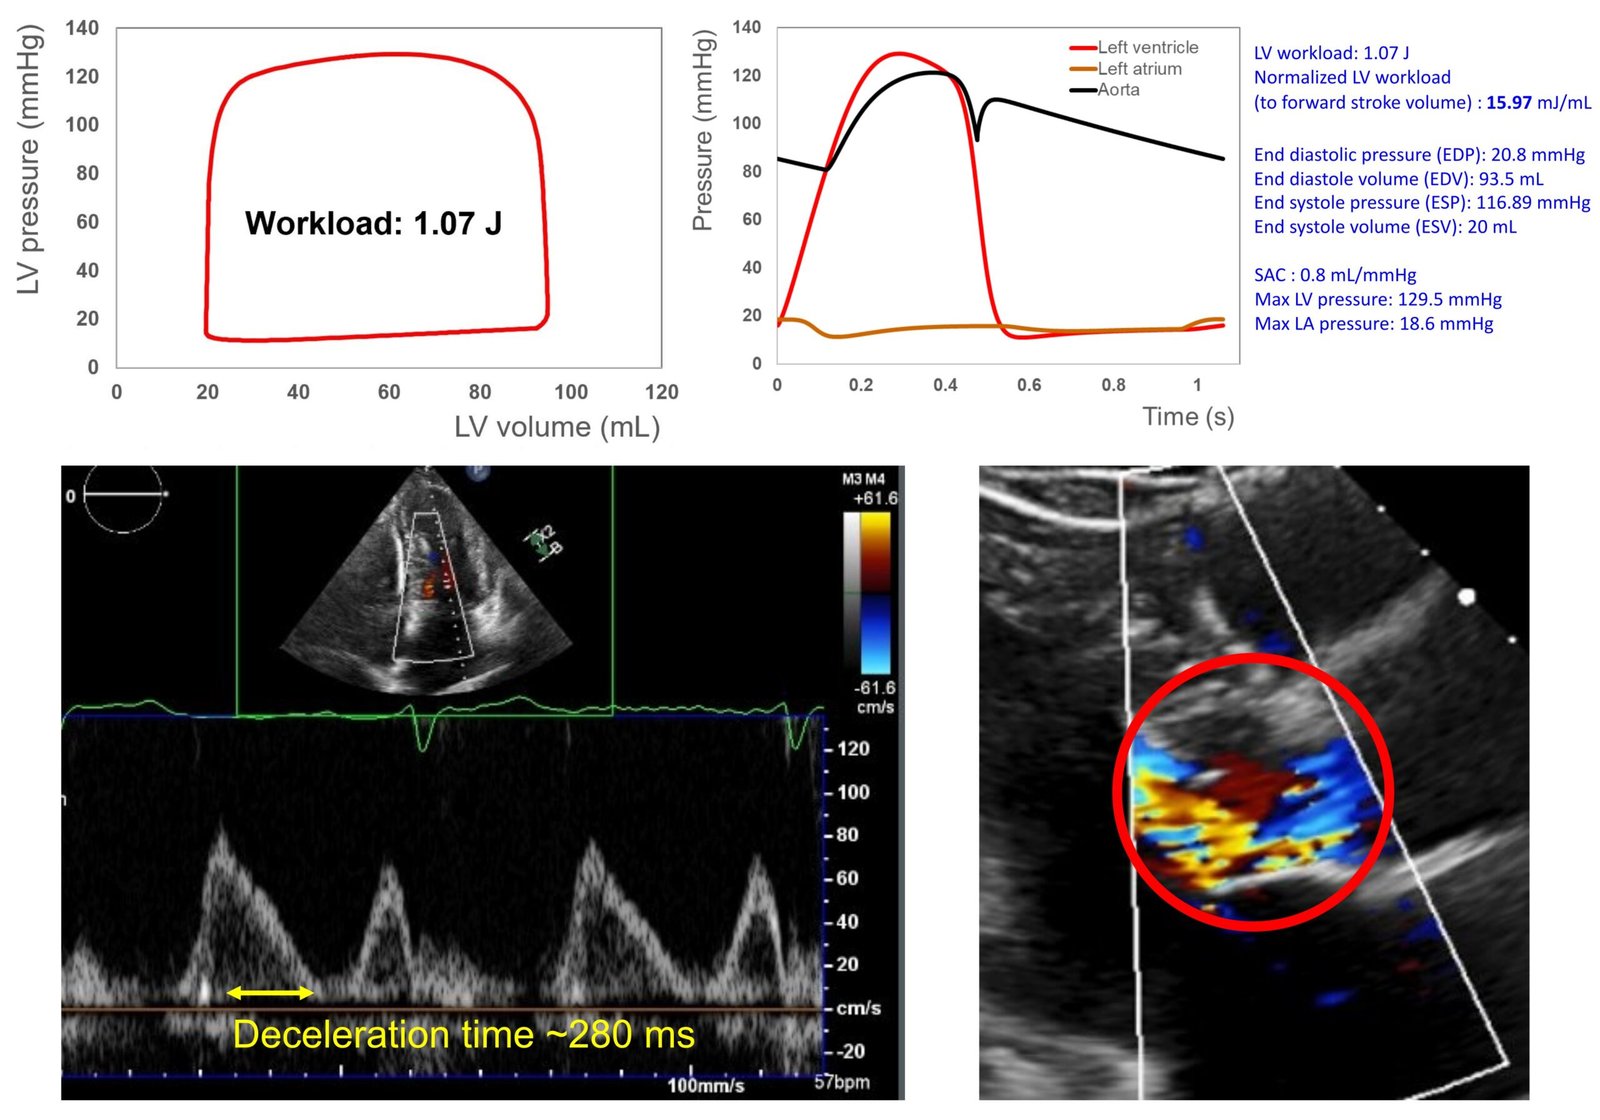

Client sample Patient 6

Doppler-based P-V loop analysis

Pre and post intervention comparison

Transcatheter mitral valve